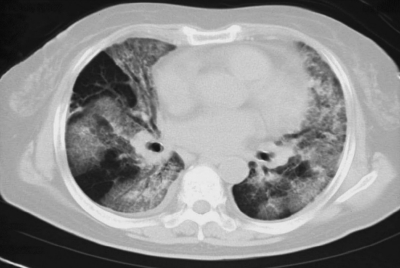

血液所見:Hb 6.2 g/dL。CRP 3.6 mg/dL。胸部エックス線写真と肺野条件の胸部CTとを別に示す。喀痰の塗抹、培養検査は一般細菌、抗酸菌ともに陰性で、結核菌の PCR 検査も陰性である。気管支肺胞洗浄液は鮮紅色で、ヘモジデリン貪食マクロファージを認める。